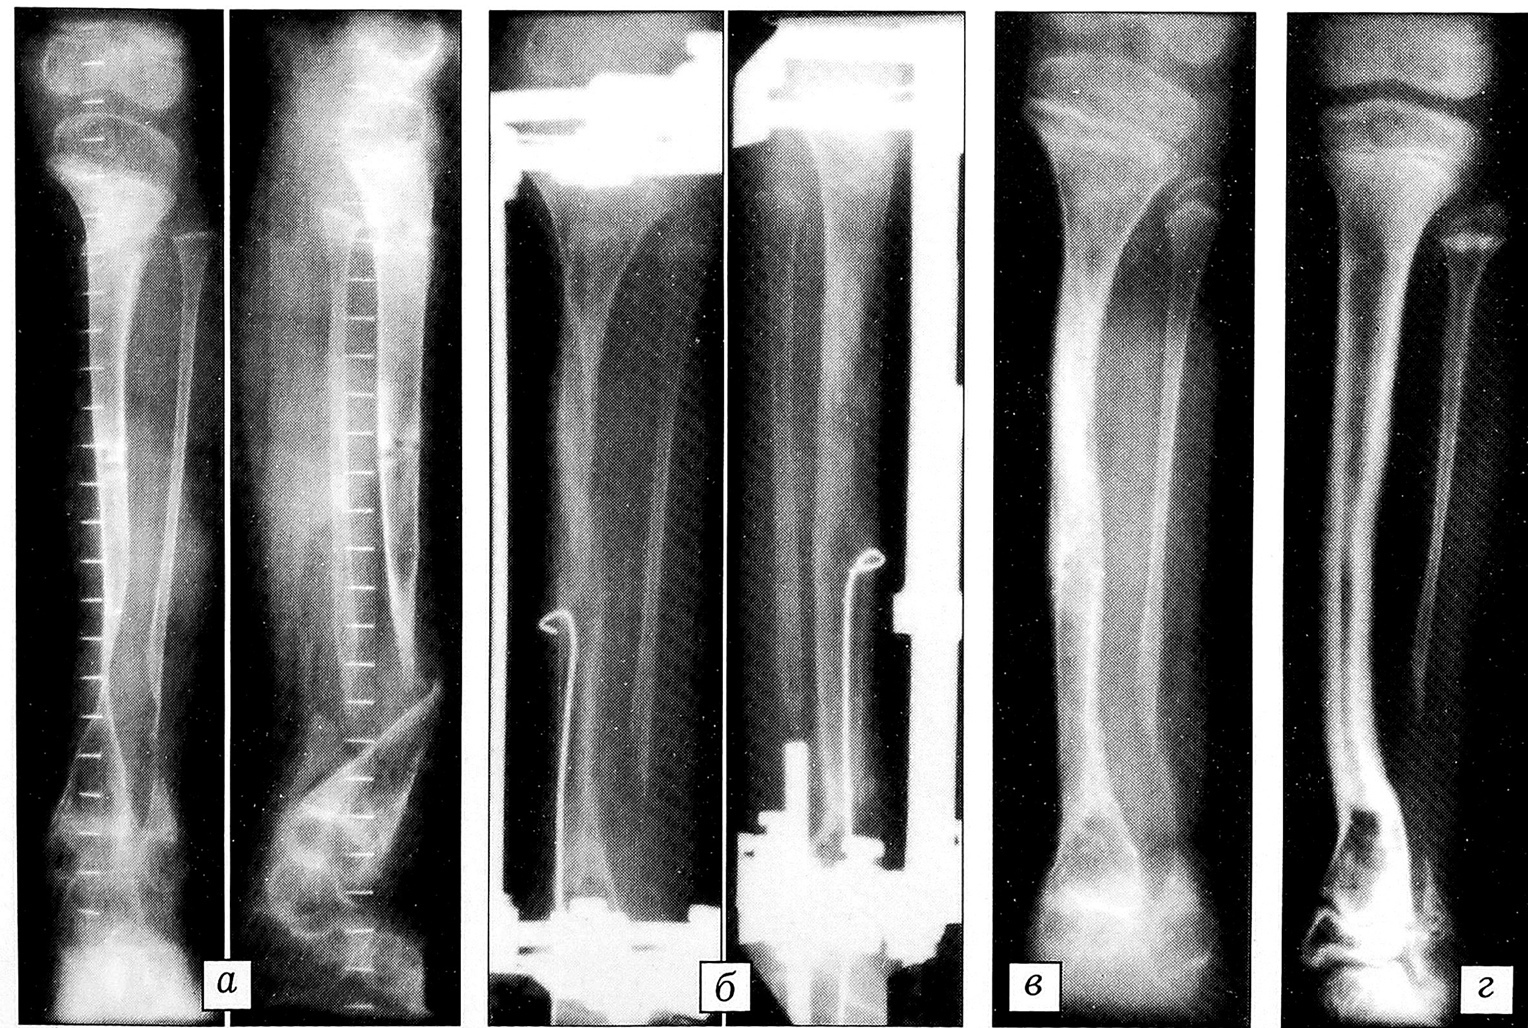

Больной К., 26 лет, поступил с посттравматическим дефектом левой большеберцовой кости 20 см (рис. 4). В условиях рубцового перерождения мягких тканей сегмента анатомическая целость голени восстановлена за счет удлинения обоих отломков большеберцовой кости, причем дистальный отломок удлинен на двух уровнях. Время перемещения сформированных фрагментов до стыка — 179 дней, общий срок дистракции — 219 дней. Срок фиксации сегмента аппаратом составил 125 дней. Достигнуто костное сращение с восстановлением длины голени.

Рис. 4. Рентгенограммы больного К. 26 лет.a — до лечения; б — в процессе остеосинтеза; в — после снятия аппарата.